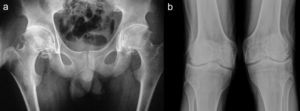

Reporte de casoPaciente varón de 17 años de edad; a los 13 años presentó dolor de cadera derecha y de rodilla izquierda. Cinco meses más tarde presentó inflamación de ambas rodillas y de interfalángicas de la mano derecha. El paciente refirió historia de dificultad al caminar desde los 3 años de edad. El examen físico mostró un adolescente con marcha anormal, escoliosis espinal y cifosis de la columna torácica. La movilidad de la columna lumbar, coxofemorales, rodillas, tobillos e interfalángicas de la mano derecha estaba severamente limitada. Las radiografías de manos y pies (fig. 1a y b), caderas y rodillas (fig. 2a y b) revelaron osteopenia difusa, ensanchamiento tubular de las epífisis y pérdida del espacio articular, sin lesiones erosivas; las radiografías de cadera y rodillas mostraron además cambios degenerativos, con cabezas femorales ensanchadas. Las vértebras torácicas y lumbares, con vértebras aplanadas e irregularidades en las mesetas vertebrales (fig. 3a y b). La proteína C reactiva y la velocidad de sedimentación globular eran normales.

La DPSR simula clínicamente una artritis idiopática juvenil en etapas tempranas1,2; sin embargo, las evidencias que establecen el diagnóstico de esta displasia ósea son la afectación articular no inflamatoria y los hallazgos radiológicos característicos, como la presencia de epífisis ensanchadas, osteoporosis generalizada y platispondilia3.